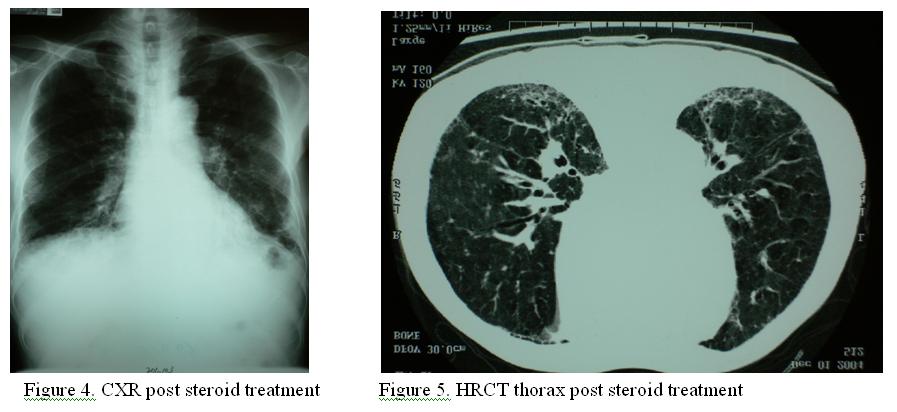

Prednisolone 50mg daily was started in mid of November, 2003. There was remarkable resolution of pulmonary shadows from both CXR and HRCT thorax (Figure 4 & 5).